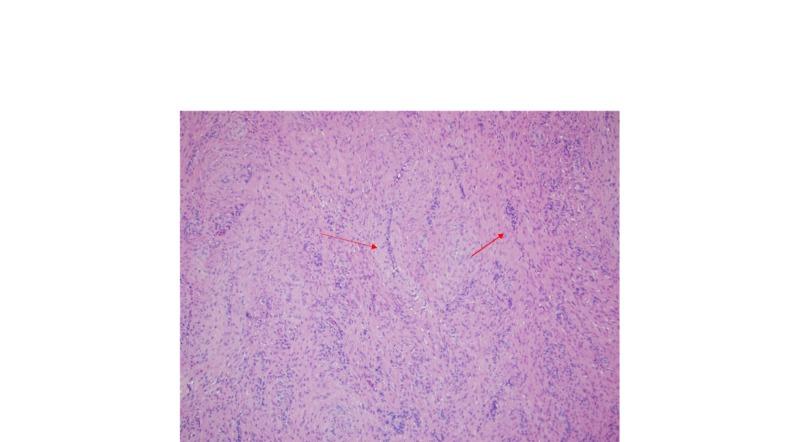

Angioleiomyoma is a benign tumor of the vascular system that is often not considered in the differential diagnosis of a painless subcutaneous nodule of the body. In this report, we present a rare case of angioleiomyoma of the phalanx in the left hand in a middle aged man. He underwent surgical excision of the mass with no complications. Given the nonspecific and indolent presentation, our case had a broad differential diagnosis including ganglion cyst and histopathological examination was warranted for definite diagnosis. At 9-month follow-up, the patient was asymptomatic with no signs of recurrence.

血管平滑肌瘤是一种血管系统的良性肿瘤,在身体无痛性皮下结节的鉴别诊断中常常未被考虑。在本报告中,我们呈现了一例中年男性左手指骨血管平滑肌瘤的罕见病例。他接受了肿物的手术切除,无并发症发生。鉴于其非特异性和惰性表现,我们的病例鉴别诊断范围广泛,包括腱鞘囊肿,明确诊断需要进行组织病理学检查。在9个月的随访中,患者无症状,无复发迹象。